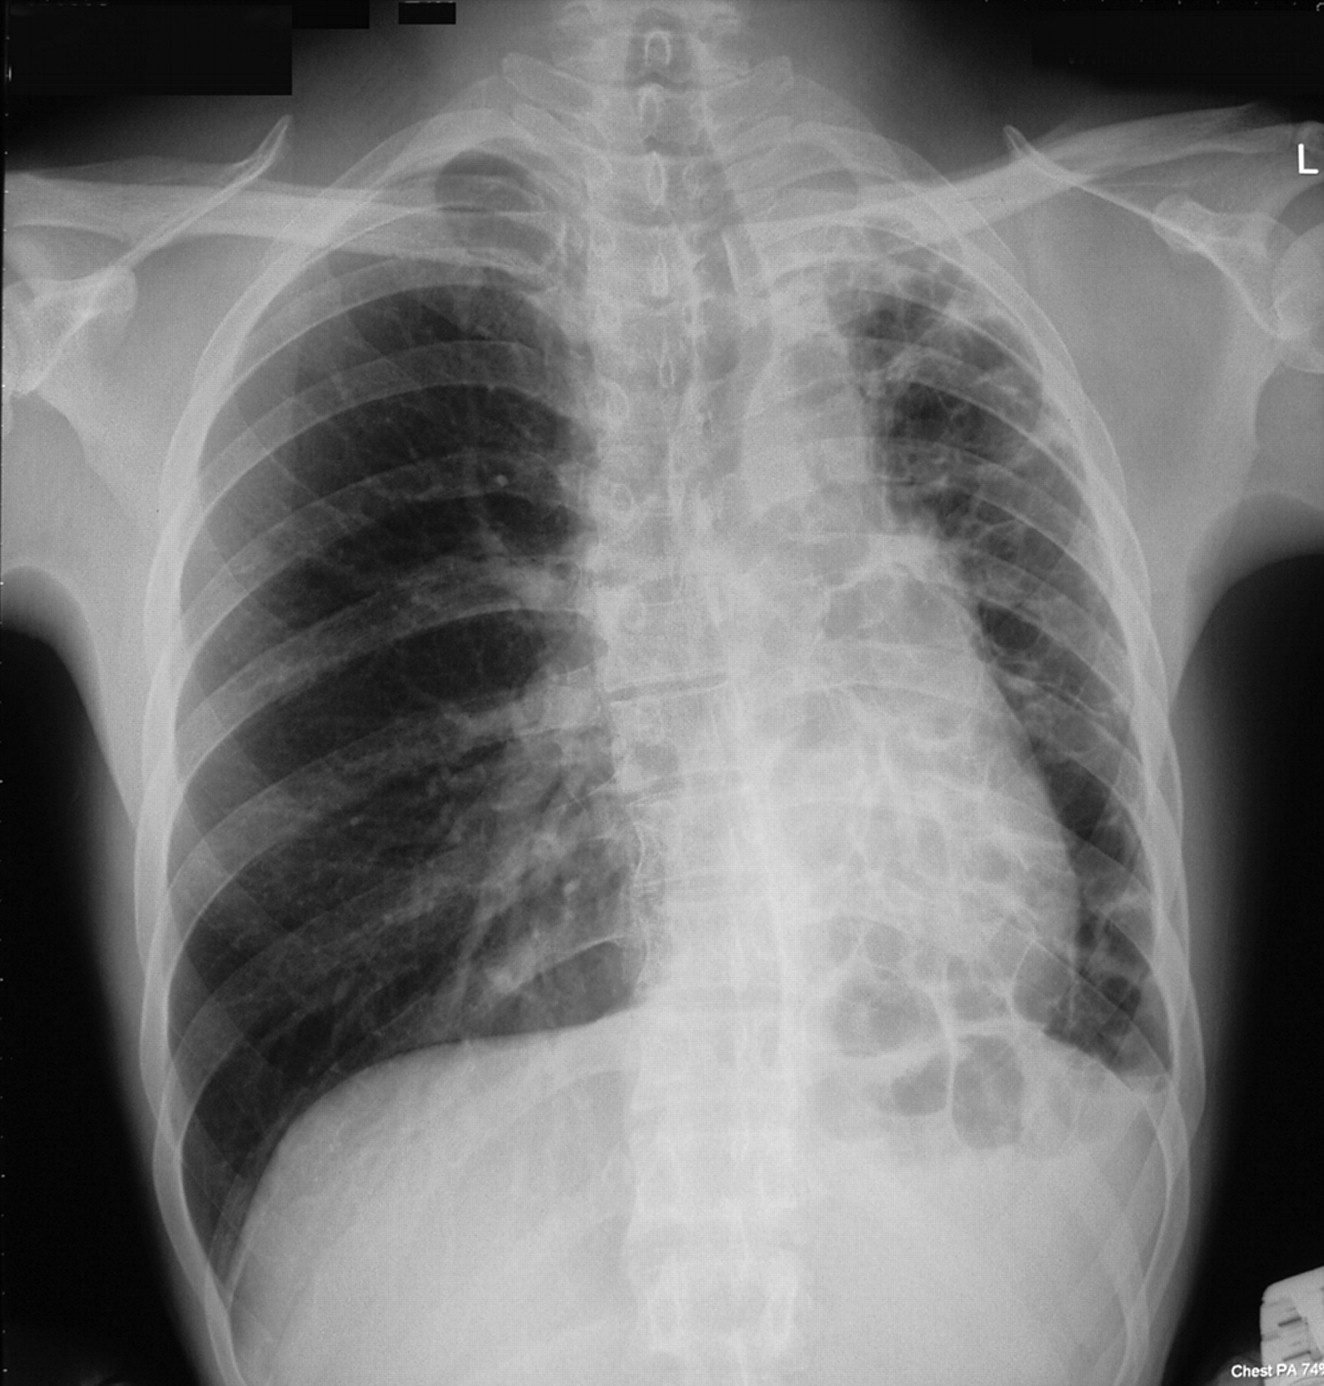

Рентгеновские снимки при врожденной эмфиземе легкого

Раздел: Визуальные уроки